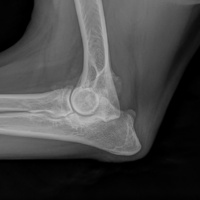

Cuattro DR HD è l'ultimo sistema radiografico digitale ad alta definizione per piccoli animali ed equini prodotto dal fornitore leader di soluzioni radiografiche digitali veterinarie.

Innovativo, veloce, efficace, sicuro e ancora più brillante: l'ultimo sistema a raggi X, Cuattro DR HD soddisfa i più alti standard nella diagnostica radiografica veterinaria.

• Visualizza i dettagli come mai fino ad ora : 17x17'’ 100 microns High definition detectors combinati con la migliore tecnologia post-elaborazione nel nostro software per immagini di altissima qualità